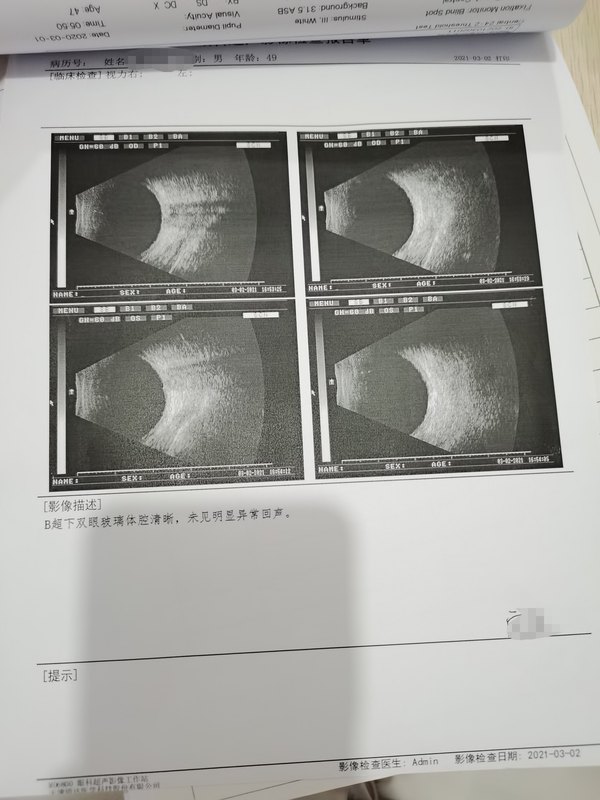

因“右眼視物模糊1月,加重10天?!比朐?,體溫:36.3℃,脈搏:72次/分,呼吸:20次/分,血壓:124/67mmHg。心肺腹(-),四肢無水腫。V0D0.04 OS1.0右眼瞼無紅腫,球結(jié)膜無充血,角膜光滑透明,前房清,瞳孔圓約3mm,對光反射存,晶體透明,眼底視盤色可,界清。眼壓:正常。